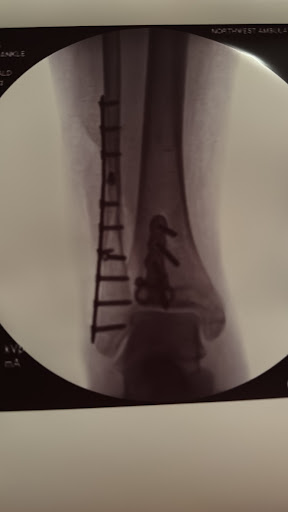

February 12, 2024I'm immensely grateful to Dr. Hegewald, his skills, and thoughtfulness, and the time I'm living in. A century ago, I would have continued my life with a clump foot. In January 2024, I've had a bad fall (doing something so mundaine like taking out the recycling) and broke my tibia and... read more fibula in in multiple pieces. The ER doctor prepared me for a long healing journey ahead as he referred me to the OSMC. The operation with Dr. Hegewald took twice as long as anticipated since he had to, literally, put the puzzle pieces that were my Fibula back together and make sure no bone debris was left behind. Usually, I like to follow my bodies cues with medications in general however Dr. Hegewald's treatment plan was so spot on, I followed it to a T managing post op pain and healing. Both, Dr. Hegewald, and Felicia have been most kind, patient, and encouraging through the entire process, helping me navigating through this experience with confidence. It is now middle of September and I'm happy to report that I've just walked 12.000 steps on Wildwood trail without pain or discomfort. I'm still healing and regaining my full ankle mobility but I can say, with confidence, that if you're in a similar position as me, you'll be in the best hands with Dr. Hegewald.

December 12, 2024I'm immensely grateful to Dr. Hegewald, his skills, and thoughtfulness, and the time I'm living in. A century ago, I would have continued my life with a clump foot. In January 2024, I've had a bad fall (doing something so mundaine like taking out the recycling) and broke my tibia and... read more fibula in in multiple pieces. The ER doctor prepared me for a long healing journey ahead as he referred me to the OSMC. The operation with Dr. Hegewald took twice as long as anticipated since he had to, literally, put the puzzle pieces that were my Fibula back together and make sure no bone debris was left behind. Usually, I like to follow my bodies cues with medications in general however Dr. Hegewald's treatment plan was so spot on, I followed it to a T managing post op pain and healing. Both, Dr. Hegewald, and Felicia have been most kind, patient, and encouraging through the entire process, helping me navigating through this experience with confidence. It is now middle of September and I'm happy to report that I've just walked 12.000 steps on Wildwood trail without pain or discomfort. I'm still healing and regaining my full ankle mobility but I can say, with confidence, that if you're in a similar position as me, you'll be in the best hands with Dr. Hegewald.

February 12, 2024When I fell and broke my ankle, my biggest concern was that I wouldn’t regain sufficient strength and stability to be able to walk as much as I like to walk. Dr. Hegewald was very reassuring. It took a plate and nine screws to repair my trimalleolar fracture. His... read more confidence, skill, and encouragement put my mind at ease. And, here I am, less than five months post-op, walking as much as I did before. I couldn’t be more pleased! Thank you, Dr. Hegewald!!